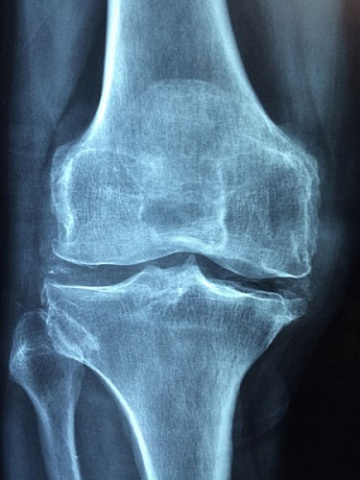

La hipofosfatasia en adultos conlleva una pérdida de mineralización que da lugar a fracturas recurrentes, fracturas femorales, antecedentes de raquitismo y dolor musculoesquelético, además de afecciones dentales. En el caso de los niños es mucho más grave, provocando incluso la muerte prematura a los pocos días de vida, daños cerebrales y problemas respiratorios. (Fuente: CIBER)